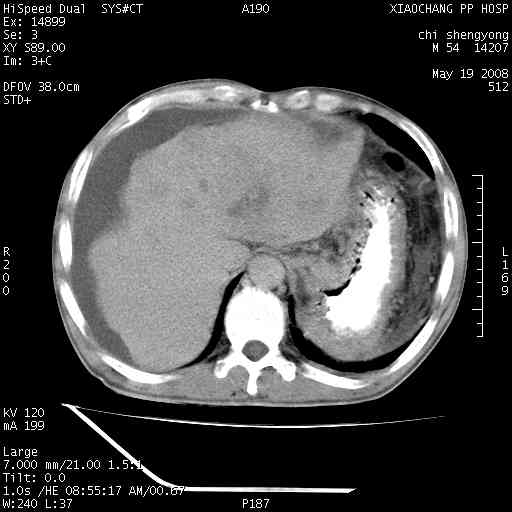

以下是引用zjzjr在2008-5-21 10:52:00的发言:[br]肝左叶巨块型肝癌伴门静脉左支瘤栓形成.肝硬化、腹水,胃底静脉曲张,脾术后改变。

以下是引用随光逐影在2008-5-21 16:20:00的发言:[br]1)肝左叶肝癌伴门静脉左支瘤栓形成,腹膜后淋巴结转移。2)肝硬化、腹水、胃底静脉曲张。3)胆囊炎。4)脾脏缺如,为切除术后所致。